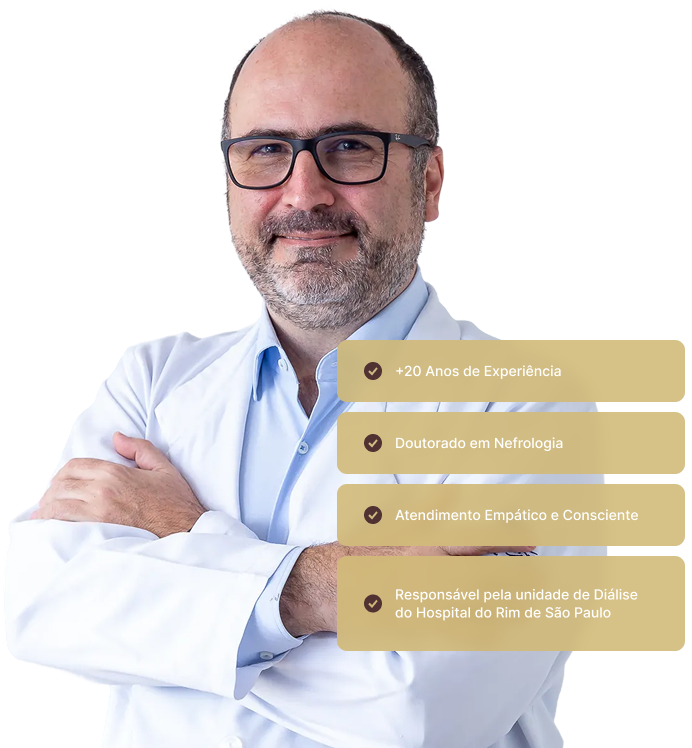

Dr. Adriano

Luiz Ammirati

Com mais de 20 anos de experiência na área de nefrologia, o Dr. Adriano Luiz Ammirati é um profissional altamente qualificado, comprometido com o cuidado especializado de pacientes renais. Formado e doutorado pela UNIFESP, ele atua em áreas cruciais da nefrologia, com destaque para o tratamento de pacientes em hemodiálise e de pacientes graves, oferecendo um atendimento humanizado e baseado em evidências.

Além de sua prática clínica, Dr. Adriano também é professor no ensino superior e em programas de pós-graduação, transmitindo seu conhecimento para a formação de novos profissionais de saúde. Seu interesse acadêmico e prático o levou a realizar um fellowship em Insuficiência Cardíaca pela Universidade de Barcelona, aprofundando ainda mais sua expertise em doenças que frequentemente afetam os rins.

Atualmente, Dr. Adriano integra a equipe da Unidade de Diálise do Hospital Israelita Albert Einstein, onde continua seu trabalho de excelência no tratamento de pacientes com doenças renais, sempre focado na melhora da qualidade de vida de seus pacientes e no avanço das práticas médicas em nefrologia.